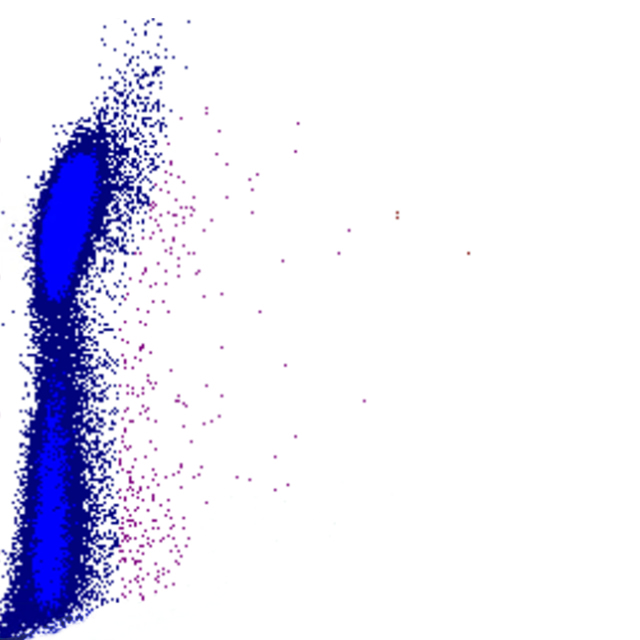

Forward Scatter

Le FSC est une mesure de la taille cellulaire : des valeurs élevées de FSC indiquent des cellules plus grandes, tandis que des valeurs plus faibles correspondent à des cellules plus petites. Les plaquettes présentent le FSC le plus bas, tandis que les monocytes, les lymphocytes plasmocytoïdes et certains blastes figurent parmi les cellules les plus volumineuses.